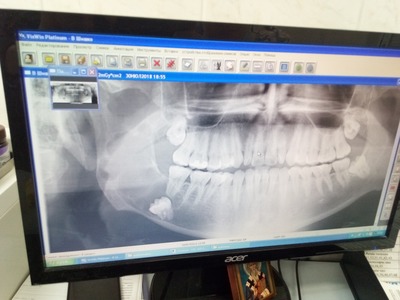

А для того, что ортопантомография (ОПТГ, обзорный или панорамный снимок зубов), является плоскостным, а значит происходит наложение каждой детали снимка послойно друг на друга. Следовательно, рассмотреть объект исследования, в частности, область зуба мудрости, расположенного рядом нижнечелюстного нерва, во всех плоскостях, под иным углом или другой проекции невозможно. КЛКТ (Конусно-лучевая компьютерная томография), напротив дает нам такую возможность.